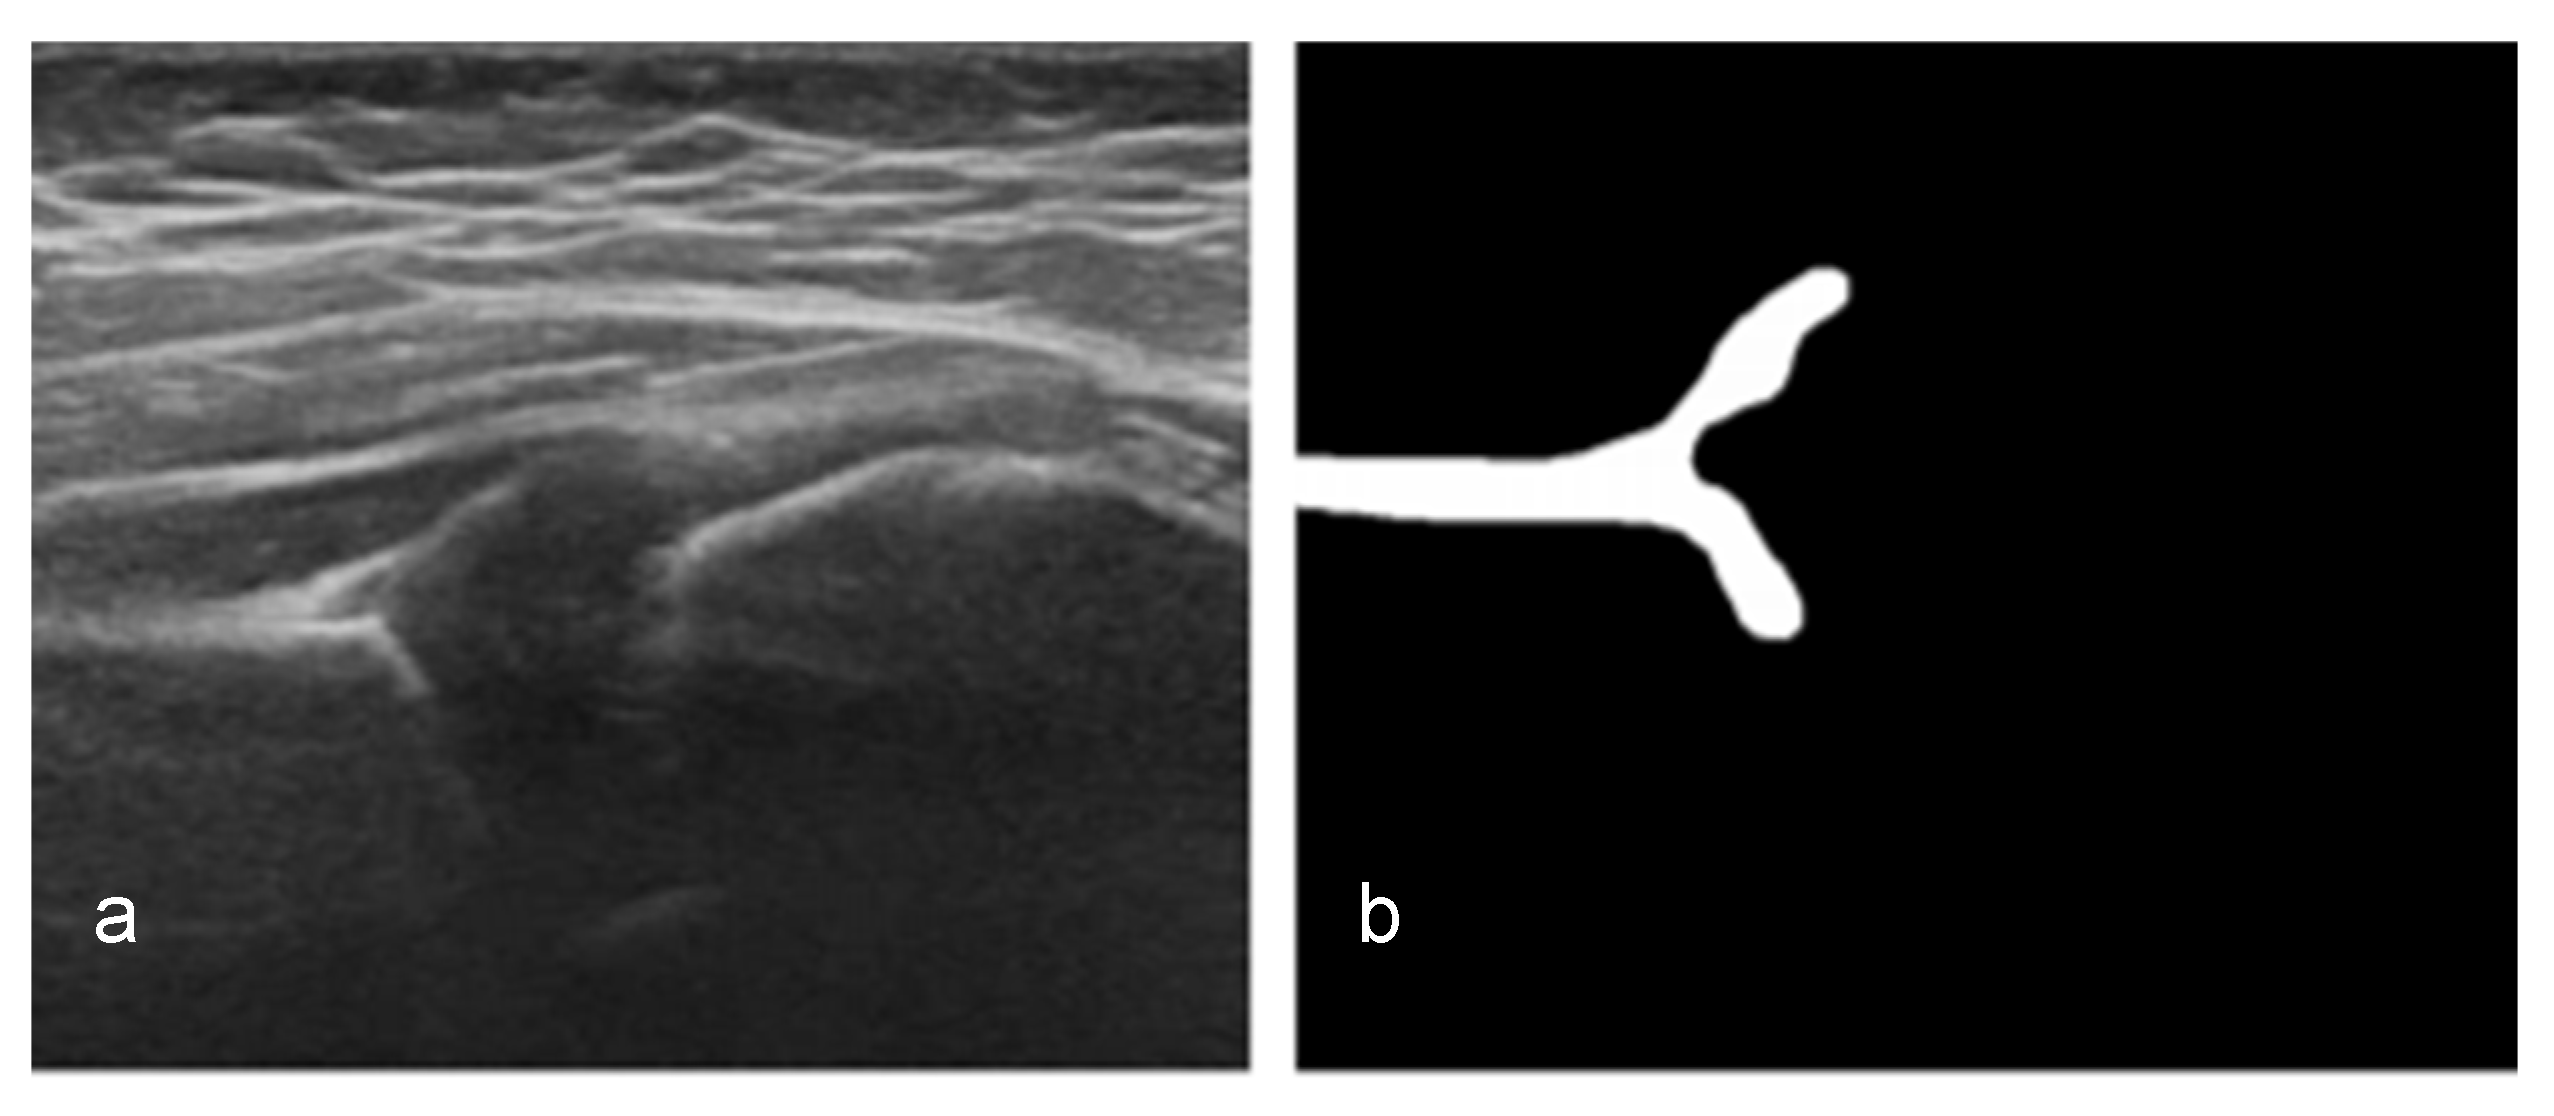

2.2.1. Segmentation